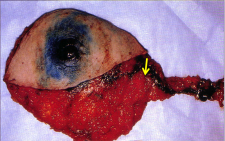

- ניתן להזריק חומר צבע הנספג במערכת הלימפתית וצובע את הבלוטות או חומר רדיואקטיבי המסמן את הבלוטות. בכל מקרה, החומר צריך להיות סגולי, כלומר להיספג רק למערכת הלימפתית. חומר הצבע מוזרק כעשר דקות לפני הניתוח סביב השאת ובניתוח ניתן לראות היטב את כלי הלימפה הצבועים ואת הבלוטות הצבועות (תמונה 51.12).

|

|

|